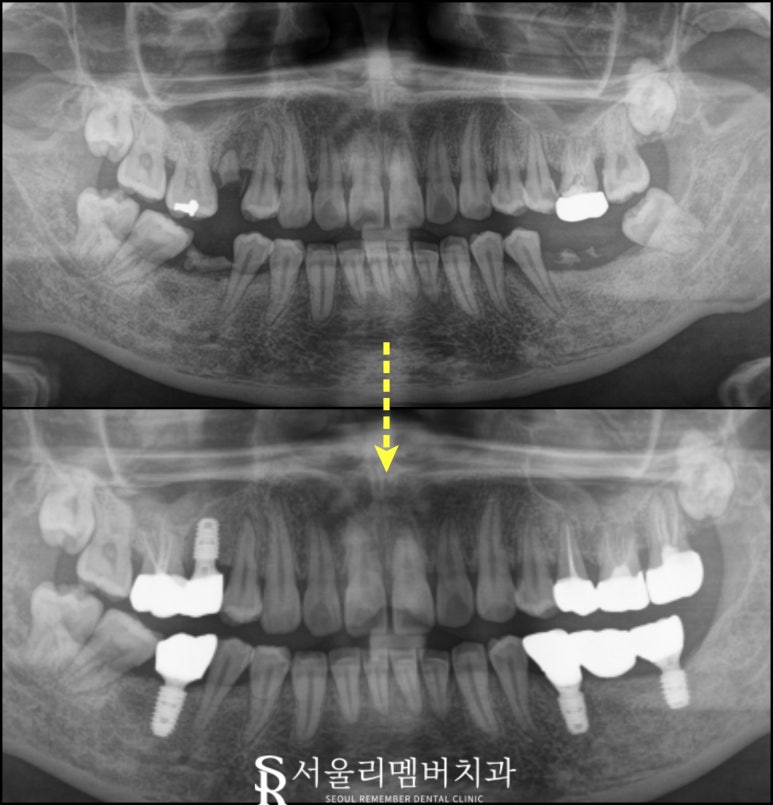

골 유착 시간을 가져주고

저희 서울대입구역 치과 자체 기공실에서

신속하게 최종 보철을 제작해 수복해 드렸습니다.

한번 보실까요?

초진 사진과 비교해 보면

더욱 균형 잡혀있는 모습을 보여주는데요.

이젠 빈 곳이 없으니

더 이상 주변 치아나 반대 치아가

움직이는 일은 없을 겁니다.